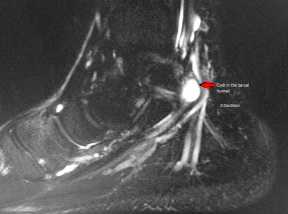

Для выявления патологий мягких тканей проводят МРТ голеностопного сустава стопы: могут быть обнаружены тендинит (дистрофия сухожилия), теносиновит (воспаление сухожилия), липомы или другие новообразования, варикозное расширение вен и кисты ганглиев.

Рис 3. МР-признаки наличия жидкостного ганглия, оказывающего патологическое давление на большеберцовый нерв.